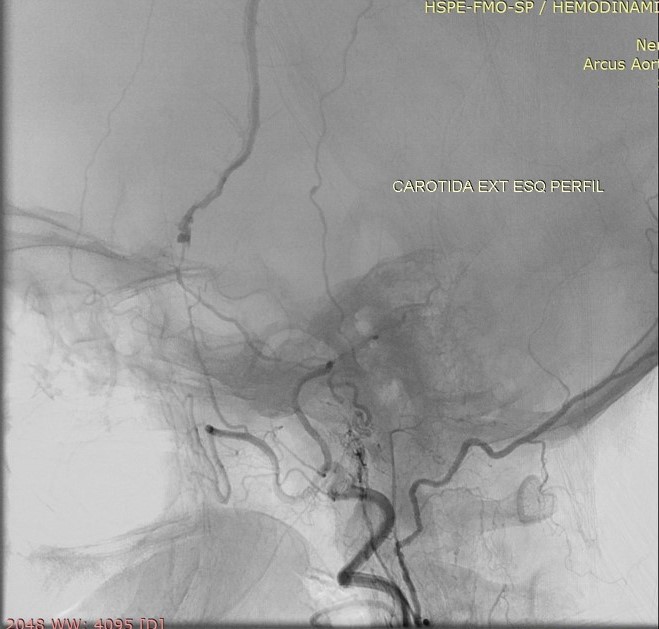

Discussão de tratamento de Fístula Arteriovenosa Dural grau I

Malformações artério venosas durais intracranianas - Discussão de caso fístula dural pós traumática grau I

Fístulas arteriovenosas durais (FAVDs) são lesões adquiridas, que consistem em uma ou mais conexões fistulosas no interior dos folhetos da dura-máter, envolvendo mais especificamente as paredes de um seio venoso dural ou as veias leptomeníngeas adjacentes.

Em 1995, Cognard et al. analisaram retrospectivamente 205 pacientes portadores de FAVDs, atendidos no período de 18 anos, em três grandes centros de referência no mundo. Algumas alterações e complementações foram propostas à classificação estabelecida anteriormente por Djindjian et al.  Na classificação publicada por Cognard et al., as lesões tipo I possuem drenagem diretamente para o interior de um seiovenoso dural, somente de forma anterógrada . As lesões tipo II são caracterizadas por elevada sobrecarga arterial e insuficiente drenagem venosa anterógrada. Ocorre, então, fluxo retrógrado ao longo do seio venoso.  Essa categoria é subdividida em três grupos,incluindo: tipo lIa com fluxo retrógrado somente no interior do seio venoso; tipo Ilb, com fluxo anterógrado no interior do seio venoso e refluxo para as veias corticais; e tipo lIa + b, com fluxo retrógrado para o seio e veias corticais. As lesões tipo III drenam exclusivamente para as veias corticais sem ectasia venosa. As lesões tipo IV drenam diretamente para as veias corticais que possuem ectasia venosa (dilatação maior que 5 mm de diâmetro). Finalmente, Cognard et al.acrescentaram um novo grupo, representado pelas lesões que drenam diretamente para as veias perimedulares espinhais, classificando-as como tipo V.